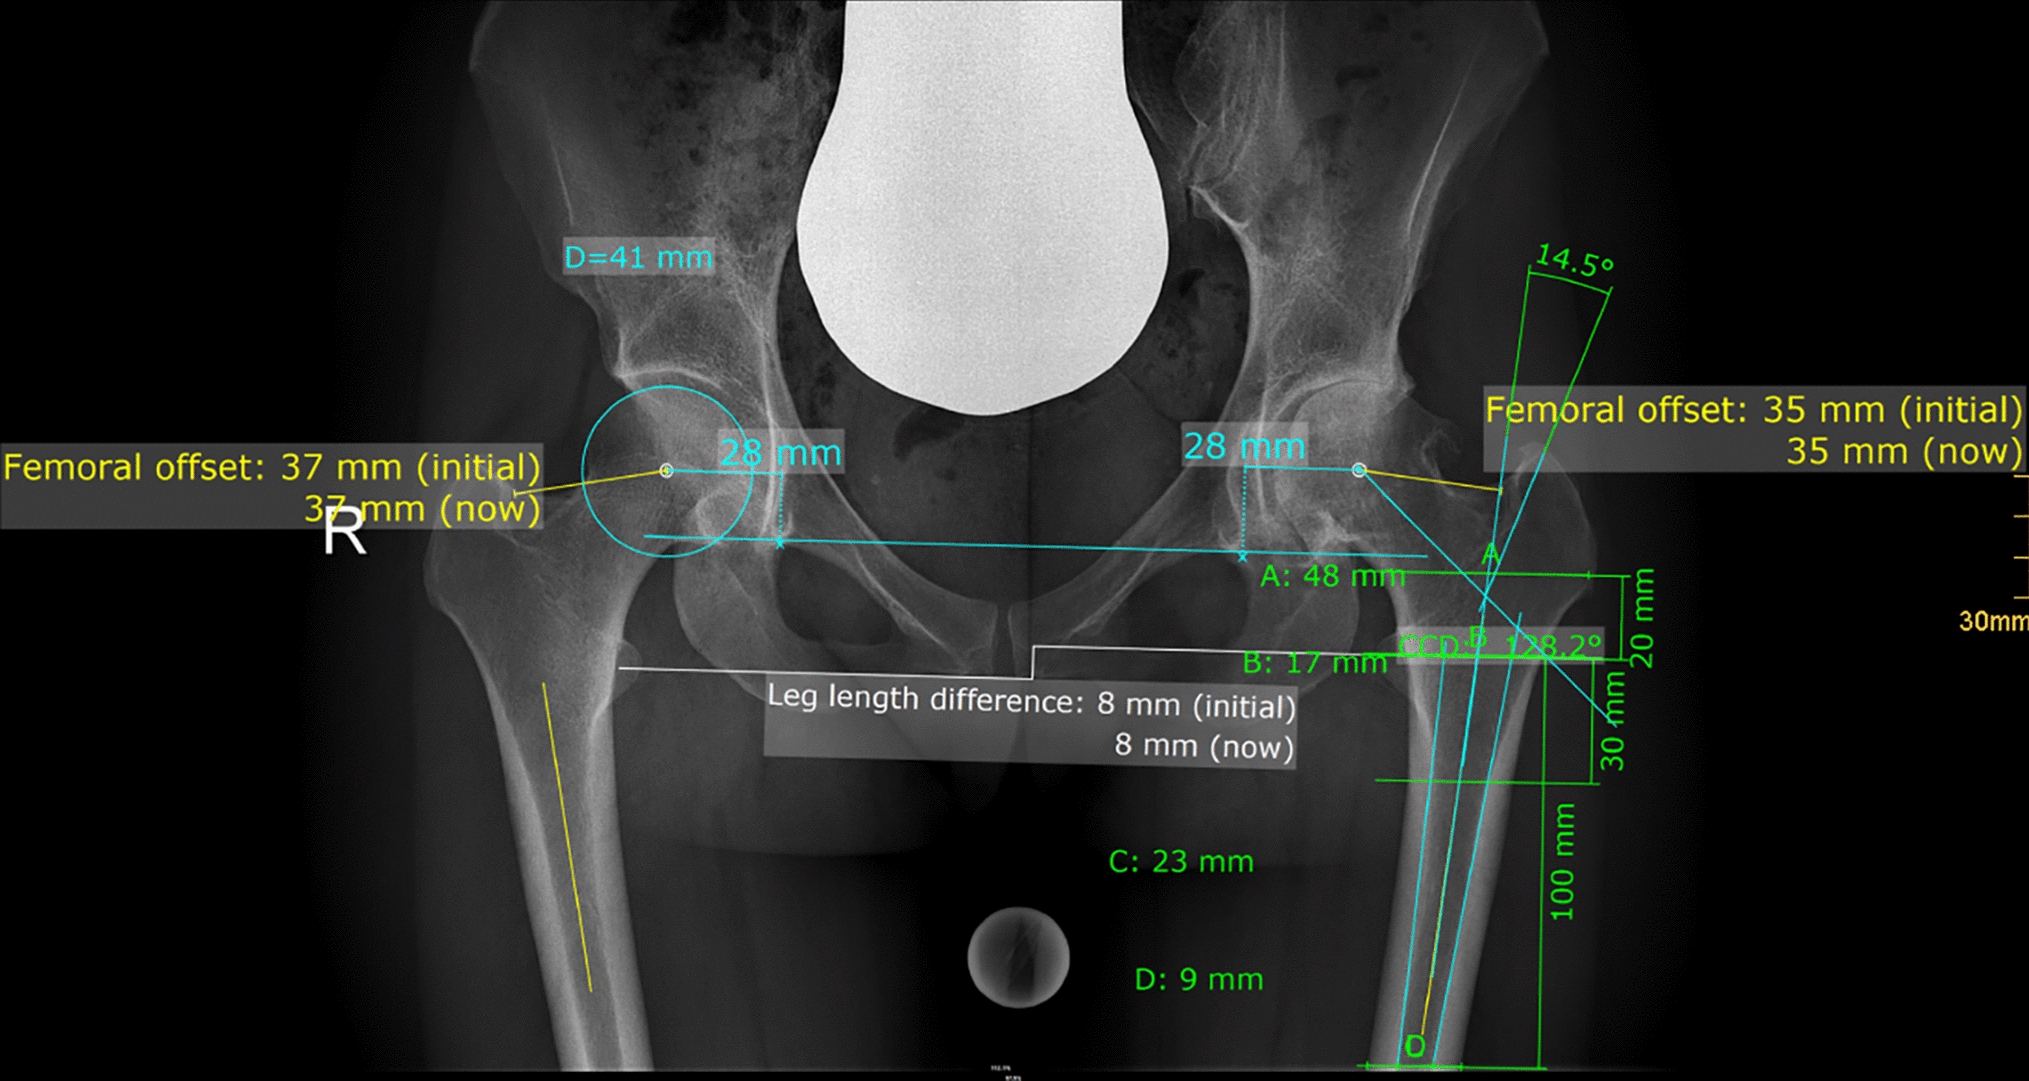

Radiographic measurement was performed on preoperative and 3 months postoperative digital low-centered AP radiographs of the pelvis [17]. Measurements were conducted independently by two reviewers (M.L., J.A.), who were not involved in the index surgery. Radiographs were taken with the patient in standing position and with both legs in 15° internal rotation with the central beam directed on the symphysis pubis [18]. To achieve an accurate measurement of the hip anatomy a double coordinate system was applied on both the preoperative and the postoperative images [1, 19]. Radiographic analysis was performed using MediCAD® Software V5.1 (Hectec GmbH, Germany). The hip center of rotation (COR) was defined using a circle tool determining the diameter of the femoral head and its center [20]. The femoral offset (FO) was determined as the perpendicular distance between the COR and the proximal femoral shaft axis (FSA) [17, 20]. Acetabular offset (AO) was measured as the perpendicular distance between the COR and line T, with T being the perpendicular line on the transteardrop line (TT) through the ipsilateral teardrop figure [17]. Hip offset (HO) was calculated as the sum of FO and AO [17]. The vertical position of the COR was measured as the perpendicular distance to line TT [21]. Radiographic leg length discrepancy (LLD) was measured as the perpendicular distance between line TT and the middle of the lesser trochanter (LT) [18]. Centrum–collum–diaphyseal (CCD) angle was determined according to M. E. Müller on the affected hip [22]. Definition of the stem axis of the implanted cementless stem was previously described for cementless straight stem [23] and for Fitmore® hip stem [24]. For enabling exact measurement of the stem axis of the implanted Fitmore® stem, a digital template of the stem size was put over the implanted stem on the postoperative X-ray. The templating software displayed the correct stem axis of the implanted Fitmore® hip stem, Fig. 3. The critical trochanter angle (CTA) was measured as described by Haversath et al. [7]. The angle crest is defined as the intersection of the femoral shaft axis and the femoral neck axis. A leg between the angle crest and the trochanter vertex is built, and the CTA is measured between this leg and the femoral shaft axis, Fig. 1. To characterize the anatomical shape of the proximal femur and the thickness of cortical bone, the canal to calcar isthmus ratio and the cortical index (CI) according to Dorr et al. [25] were determined. A high CI indicates a thick cortical bone [25]. Additionally, the canal flare according to Noble et al. [26] was determined. The stem alignment was measured as the difference in degrees between the anatomic femoral shaft axis and the vertical stem axis [27]. On preoperative X-rays FO, AO, HO and LLD were measured bilaterally, while CCD angle, CI, Canal Flare Index and canal to calcar ratio were measured unilaterally on the affected hip. Complete preoperative measurements are also shown in Fig. 2.

Fig. 2

Preoperative measurements: HO, FO, AO, LLD (all bilaterally), CTA, CCD angle, Canal Flare Index, Cortical Index, canal to calcar ratio (all unilaterally)

Bild vergrößern